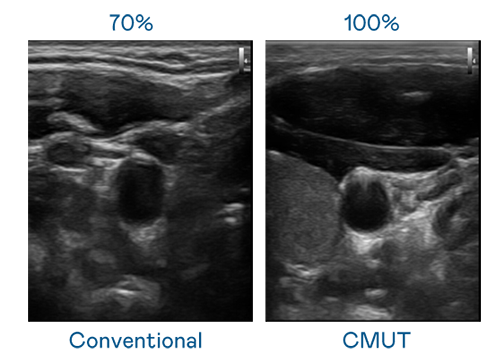

CMUT 技術是一種用電容式微機電元件來產生超音波訊號的技術。與傳統 PZT 壓電式技術相比,CMUT 頻寬增加 30%,更寬頻的超音波訊號讓影像解析度大幅提升,是實現高影像品質醫療超音波掃描、促進精準醫療發展的關鍵技術。

超音波影像的解析度高低,首先取決於探頭能發出的訊號頻寬。OG视讯 CMUT 可提供高清晰的超音波訊號,提供高頻寬、高靈敏度、影像紋理細節更高的超音波影像,協助醫護人員縮短影像判讀時間及利用精準的醫療影像進行診斷。